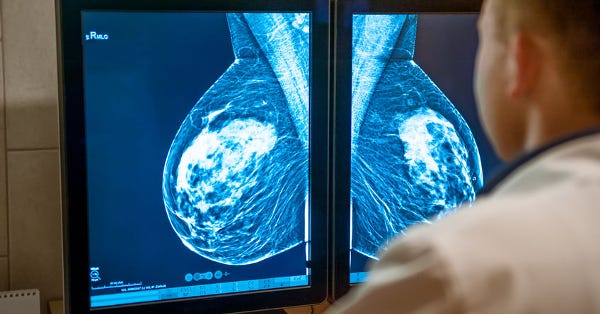

Our landmark 2012 article, Mammograms Linked to an Epidemic of Misdiagnosed Cancers, revealed that over 1.3 million women had undergone unnecessary treatments for DCIS due to mammogram-driven overdiagnosis. This critique was part of our broader effort to shed light on the pitfalls of mammography, which often identifies abnormalities that remain non-invasive, and which include planting the radiological seed of breast cancer malignancy into countless women who otherwise would not be at risk of developing it.

The recently published COMET (Comparing an Operation to Monitoring with or without Endocrine Therapy) study marks a pivotal moment in redefining DCIS. Its findings demonstrate that women who choose active monitoring experience (i.e. watchful waiting) no greater likelihood of developing invasive cancer within two years compared to those undergoing surgery.

As early as 2012, our article 30 Years of Breast Screening: 1.3 Million Wrongly Treated highlighted the overdiagnosis epidemic caused by classifying DCIS as "stage-zero breast cancer." This misclassification has led countless women - literally millions - to undergo surgeries, radiation, and other invasive treatments for a condition that often remains non-threatening.